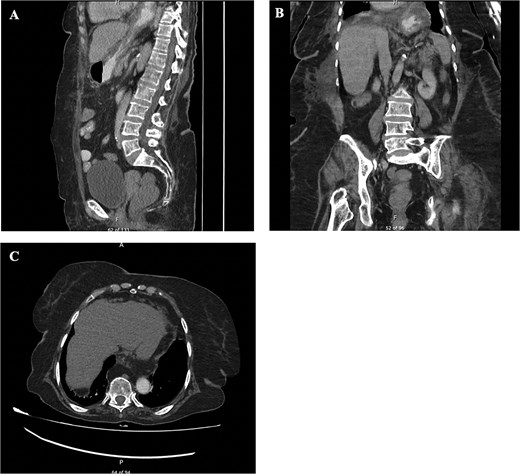

Upon admission, the patient appeared ill, and vital signs were as follows: temperature 37°C, blood pressure 180/80 mmHg, heart rate 82 bpm, oxygen saturation 92%, and random blood sugar 149 mg/dl. On abdominal examination, tenderness was noted in the epigastric and left hypochondriac regions. Chest examination revealed equal bilateral air entry. Venous blood gas showed uncompensated respiratory acidosis with pH: 7.28, PaCO₂: 59 mmHg, and HCO₃−: 24 mmol/L. Routine laboratory investigations were within normal limits. An abdominal ultrasound was performed, but the findings were inconclusive. An abdominal computed tomography (CT) scan demonstrated a large hiatal hernia, with a dilated gastric fundus and pylorus herniating through the hiatus into the thoracic cavity. With internal hyperdense content, representing food particles or hemorrhagic components. It was causing a mass effect on the mediastinal structures. Gastric volvulus's suggestive finding was the marked gastric distention with two distinct areas of distention, consistent with the torsion of gastric volvulus (Fig. 1). Esophagogastroduodenoscopy (EGD) revealed a twisted stomach along its central axis, filled with food and coffee ground content, and the pylorus could not be visualized, suggesting gastric volvulus.

CT finding. (A) CT scan of abdomen, sagittal view. (B) CT scan of abdomen, coronal view. (C) CT scan of abdomen, axial view. Showing a large hiatal hernia with dilated gastric fundus and pylorus. With internal hyperdense content, representing food particles or hemorrhagic components. It is causing a mass effect on the mediastinal structures. Gastric volvulus's suggestive finding is the marked gastric distention with two distinct areas of distention, consistent with the torsion of gastric volvulus.